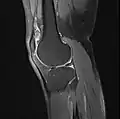

MRI

Both anterior cruciate ligament (ACL) and posterior cruciate ligaments (PCL) are hypointense on both T1 and T2 weighted images of MRI. However, some high signal striations are often seen at the distal part of the ACL, making ACL higher intensity than PCL on MRI scans.[17]